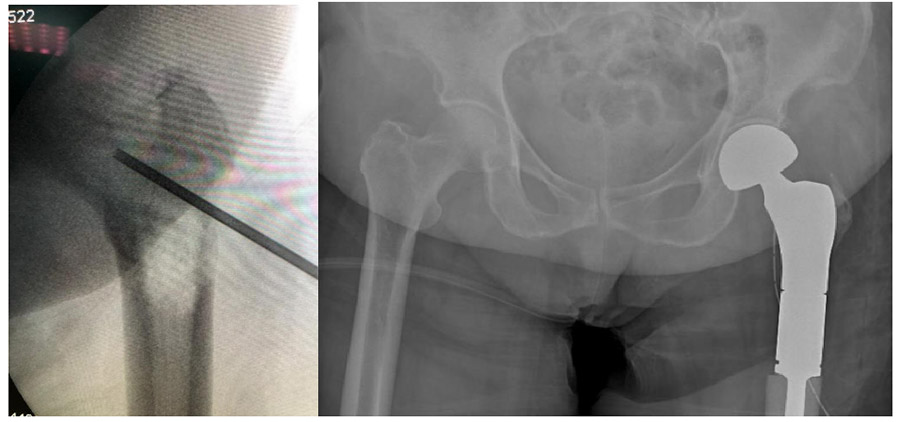

During and after the biopsy: The fluoroscopy shows the biopsy procedure, and the postoperative X-ray shows the implantation of a left proximal femur tumor prosthesis.